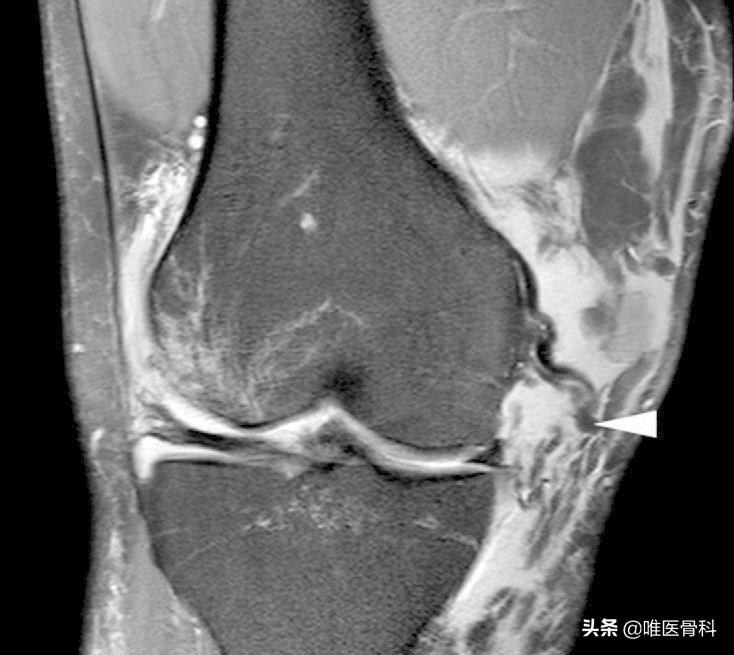

3)膝关节核磁共振:可以比较直接的看到膝关节内、外侧副韧带的损伤程度,同时可以显示是否合并有半月板或交叉韧带的损伤。